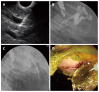

Methods: A novel dedicated device for one-step EUS-guided biliary drainage system (DEUS) introducer has size 3F tapered catheter with size 4F metal tip for simple puncture of the intestinal wall and liver parenchyma without graded dilation. A self-expandable metal stent, consisting of both uncovered and nitinol-covered portions, was preloaded into DEUS introducer. After establishment of a biliary dilatation model using endoscopic hemoclips or band ligation with argon plasma coagulation in 9 mini-pigs, EUS-BD using a DEUS was performed following 19-G needle puncture without the use of fistula dilation devices.

Results: One-step EUS-BD was technically successful in seven pigs [7/9 (77.8%) as intention to treat] without the aid of devices for fistula dilation from the high body of stomach or far distal esophagus to the intrahepatic (n = 2) or common hepatic (n = 5) duct. Primary technical failure occurred in two cases that did not show adequate biliary dilatation. In seven pigs with a successful bile duct dilatation, the technical success rate was 100% (7/7 as per protocol). Median procedure time from confirmation of the dilated bile duct to successful placement of a metallic stent was 10 min (IQR; 8.9-18.1). There were no immediate procedure-related complications.